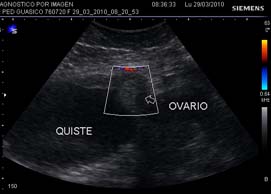

<body><![CDATA[<p align="center">&nbsp;</p>     <p align="justify"><font size="2" face="Verdana, Arial, Helvetica, sans-serif">De los cinco casos diagnosticados preoperatoriamente   como torsi&oacute;n de ped&iacute;culo de quiste anexial, en el 80% se realiz&oacute; un diagn&oacute;stico   correcto (4/5). En todos los casos de torsi&oacute;n se pudo identificar   preoperatoriamente el signo directo de torsi&oacute;n de ped&iacute;culo (4/4). En un caso   (1/5) de paciente embarazada de siete semanas que acusaba la triada cl&aacute;sica, se   observ&oacute; que el quiste anexial ten&iacute;a flujo vascular muy escaso en su pared, que   fue&nbsp; interpretado como un signo indirecto de torsi&oacute;n de ped&iacute;culo (Figura 1), el   hallazgo intraoperatorio no evidenci&oacute; tal torsi&oacute;n. En un caso (1/4) de torsi&oacute;n   de ped&iacute;culo se identific&oacute; se&ntilde;al Doppler color normal en la pared del quiste. </font><font size="2" face="Verdana, Arial, Helvetica, sans-serif">Independientemente de la   edad gestacional, todos los casos de torsi&oacute;n de ped&iacute;culo (4/4) presentaron   estado nauseoso y v&oacute;mitos. Se encontr&oacute; leucocitosis en un solo caso. No se   encontr&oacute; ning&uacute;n caso de fiebre. A los cuatro pacientes con torsi&oacute;n de ped&iacute;culo   se les realiz&oacute; la t&eacute;cnica tradicional anexectom&iacute;a sin destorsi&oacute;n del lado comprometido. Se realiz&oacute; quistectom&iacute;a en el caso falso positivo. </font></p>     <p align="justify">&nbsp;</p>     <p align="center"><img src="/img/revistas/gmb/v41n1/a02_figura1.jpg" width="439" height="309"></p>     <p align="center"><font size="2" face="Verdana, Arial, Helvetica, sans-serif">Figura 1. Caso falso positivo en paciente con sospecha de torsi&oacute;n de ped&iacute;culo de quiste anexial; el Doppler color y power angioR no detectaron flujo en su pared a pesar de la optimaci&oacute;n de las ganancias para flujo lento.</font></p>     <p align="center">&nbsp;</p>     <p align="justify"><font size="2" face="Verdana, Arial, Helvetica, sans-serif">El diagn&oacute;stico   histopatol&oacute;gico inform&oacute; lesiones benignas en todos los casos (5/5), (Tabla 2).   </font></p>     <p align="center"><font size="2" face="Verdana, Arial, Helvetica, sans-serif">Tabla 2. Diagn&oacute;stico histopatol&oacute;gico de cirug&iacute;a por quiste anexial torcido y embarazo.</font></p>     <p align="center"><img src="/img/revistas/gmb/v41n1/a02_tabla2.jpg" width="304" height="118"></p>     <p align="center">&nbsp;</p>     ]]></body>